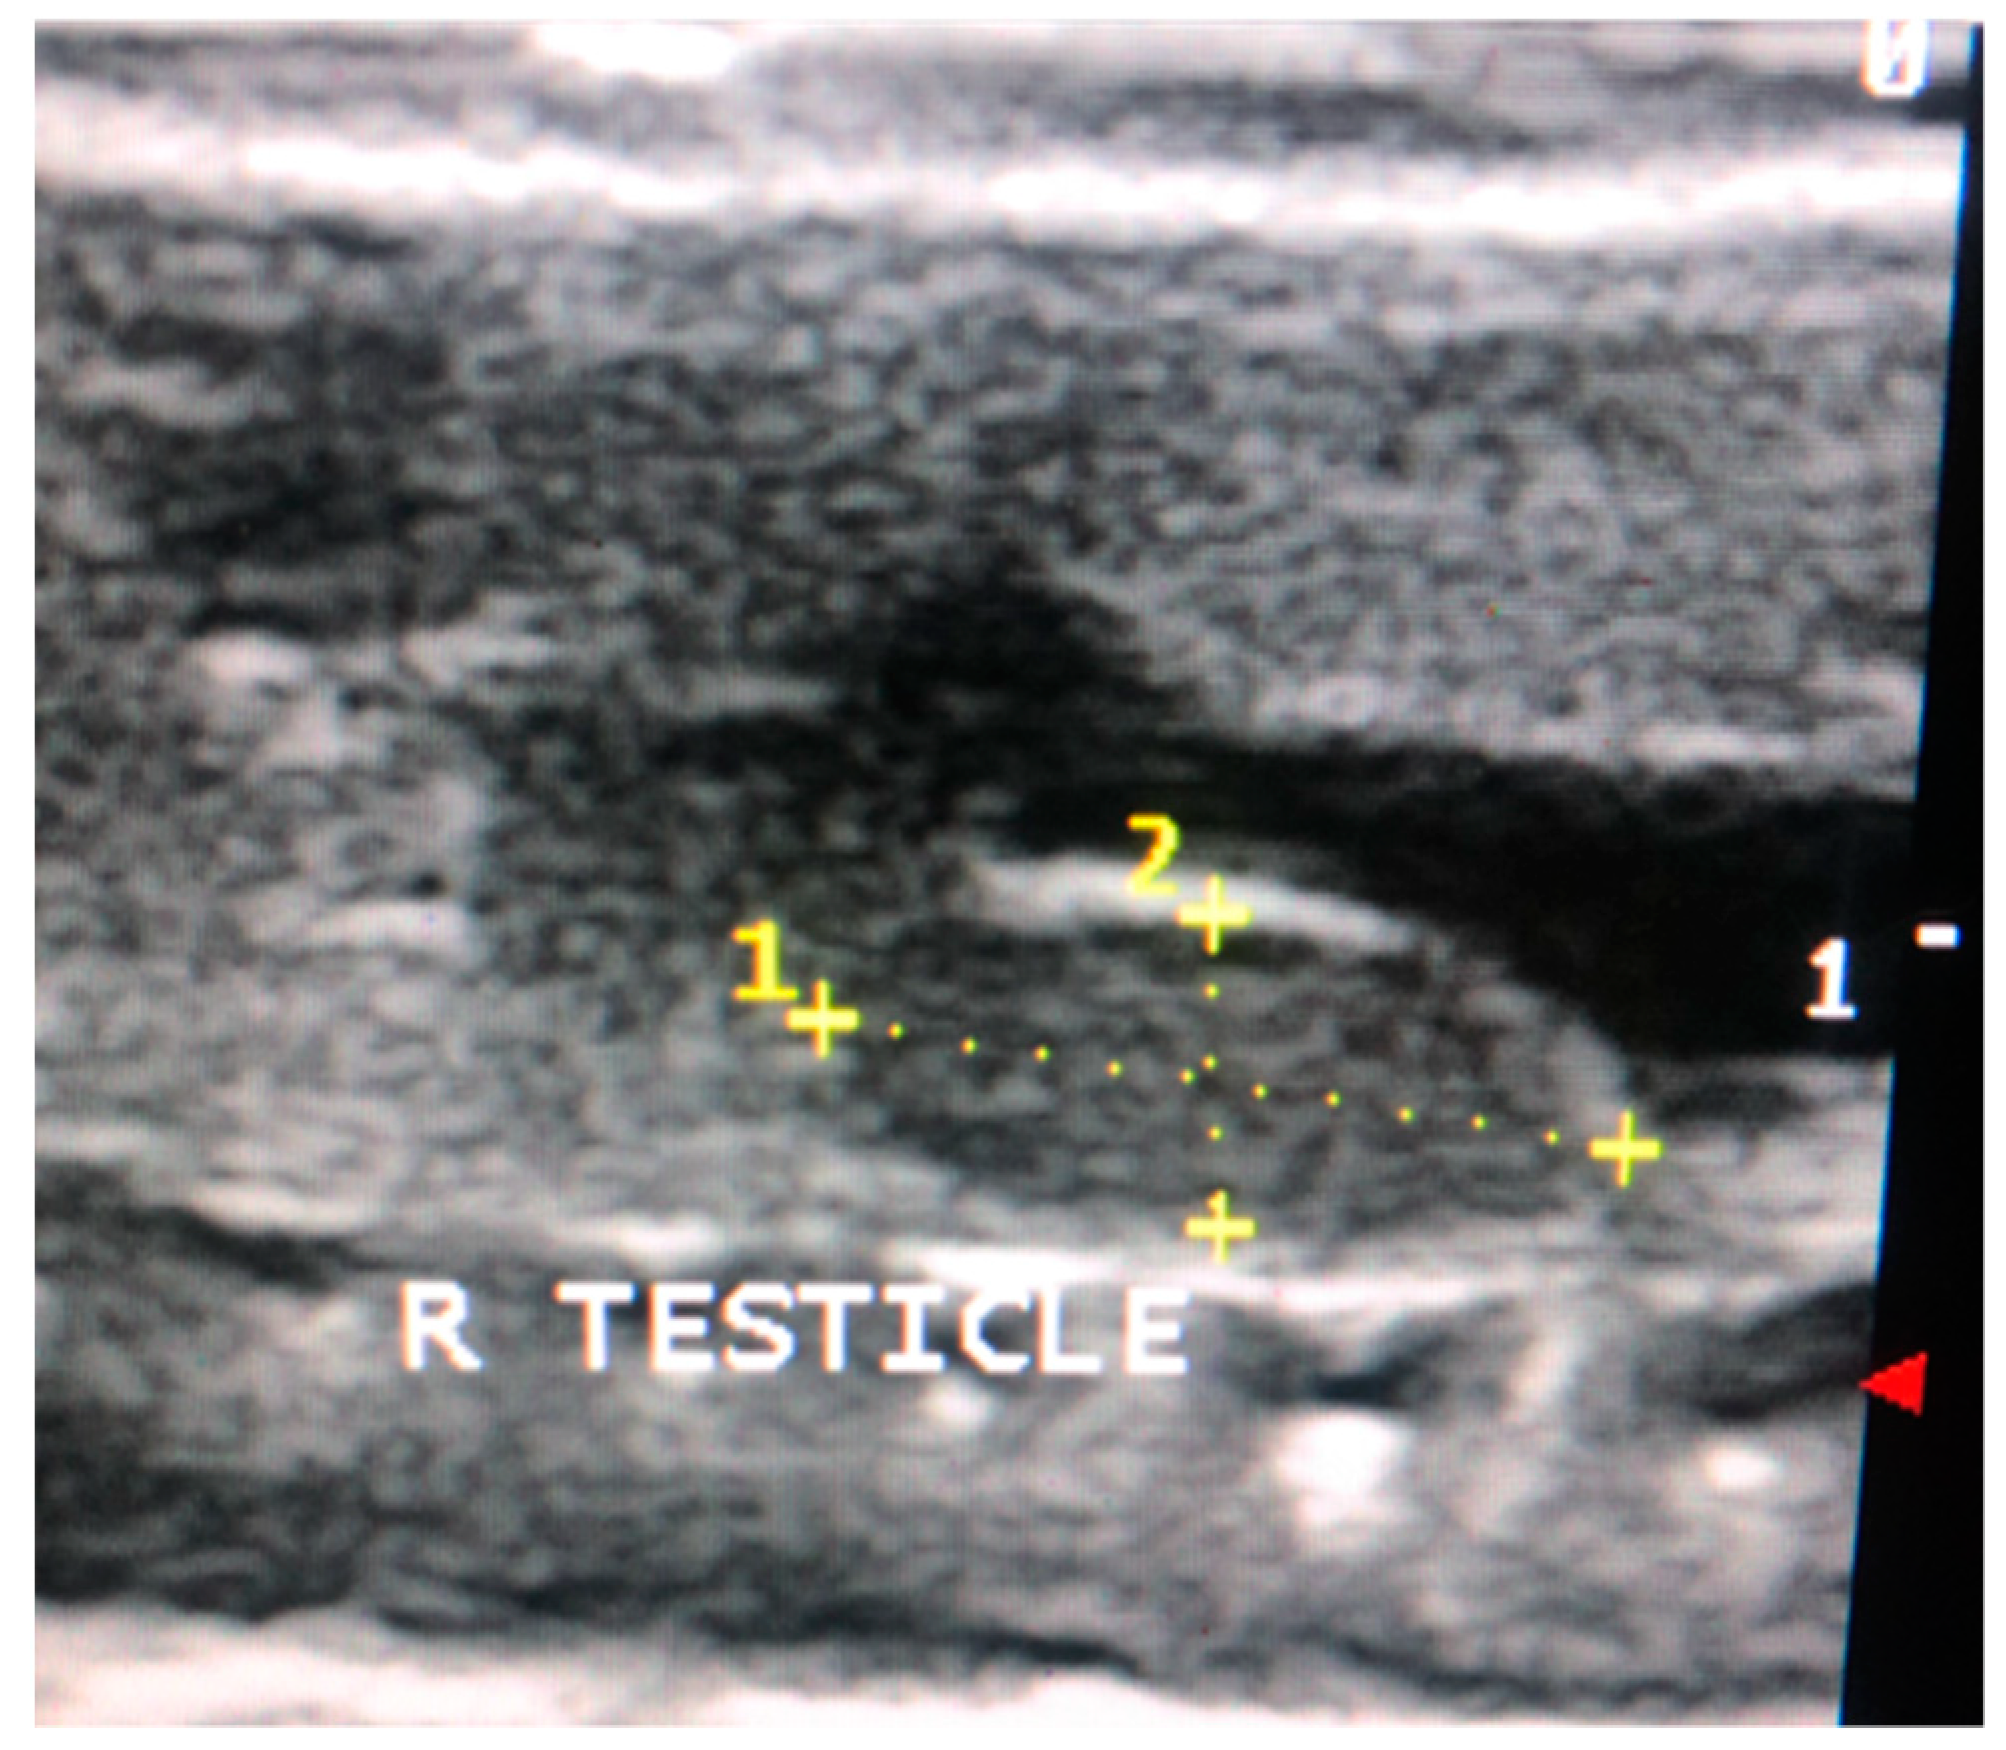

2.5. Non-Invasive Testicular Measurement

Testicular measurements of the right testicle were recorded using the Sonoscape S8 (Sonoscape, Centennial, CO, USA) with the 10–15 mHz linear array hockey stick probe as previously described (Figure 1) [12,41]. The right testicle was selected for measurement because it was more easily visualized on ultrasound; visualization of the left testicle was challenging due to superimposition of the gastrointestinal tract. Testicular length and width were recorded on days 0, 21, 42, and 63 of the study (Figure 2). The distance from the cranial to caudal poles of the testicle represented the length. Width was measured in the same view and included the distance from the dorsal to ventral borders of the testicle at its midpoint. Testicular volume was estimated using the following equation: V(mm3) = 0.52 LW2 [42].

Testicular volume by ultrasound was positively correlated (R: 0.672, p < 0.001) to post-surgical testicular volume. Post-surgical testicular volume was always higher than ultrasound measured testicular volume, except for one case. There was no significant difference in testicular volume difference between treatments (F = 0.923, p = 0.413). On average, post-surgical testicular volumes were 1.7 ± 0.62 (min–max: 0.13–2.54) times larger than ultrasound measured testicular volumes.

Testicular volume as measured on ultrasound was positively correlated to the post-surgical testicular volume, suggesting that ultrasound is a viable option for non-invasive monitoring of testicular volume in a small lizard species. Ultrasound was initially selected by the authors as a non-invasive method for measuring testicle size to develop a clinical, ante-mortem method to assess the reproductive cycles of male reptiles. Previous studies evaluating the effects of exogenous hormone administration on testicle size and function have relied on post-mortem measurements to determine their effectiveness [19,21,22,23,24,28,29,30,31,38,39,52,53]. By using ultrasound, it is possible to conduct these types of studies on threatened and endangered species. The equation used in this study to estimate testicular volume was based on the volume of an ellipsoid [42] and only requires two measurements (length and width) to estimate volume. This was advantageous because obtaining a second image to evaluate testicle width was challenging in these small lizards. This method for obtaining non-invasive testicular measurements was also found to be effective in veiled and panther chameleons [41]. However, in contrast to the chameleon study, the right testicles of all leopard geckos were removed, weighed, and measured to calculate actual testicular volumes, allowing for the validation of this equation and comparison between gross and ultrasound measured testicles. Actual testicular volumes were found to be higher than ultrasound measured testicular volumes (except in one animal); thus, ultrasound measurements may underestimate actual volume. Reptile testes are intracoelomic, elongated, and cylindrical in shape [54]; lie dorsocaudal to the liver; are suspended by the mesorchium [55]. Due to their position in the body cavity, accurate identification of the testicle borders may be reduced by the super-imposition of the gastrointestinal tract, urinary bladder, liver, and intra-abdominal fat pads. Initially, the authors of this study had planned to measure both testicles via ultrasound in each animal, and then randomly remove either the left or right testicle for histopathologic assessment. However, the left testicle was often difficult to visualize due to interference from the gastrointestinal tract, thus, the more consistently visualized right testicle was selected for routine measurement and histologic assessment in all geckos.